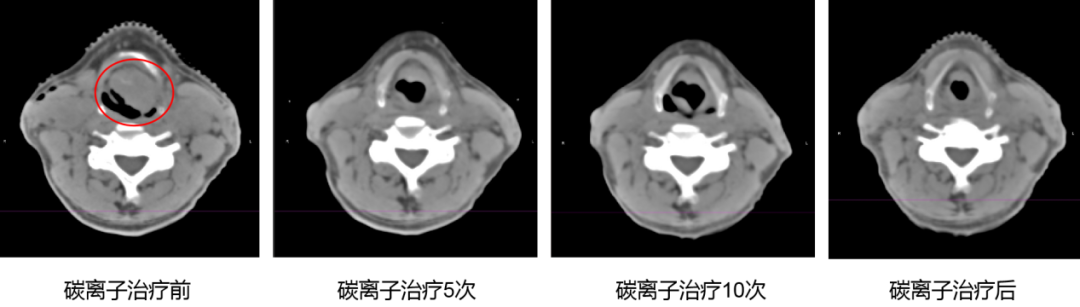

A 65-year-old male patient was diagnosed with Laryngeal Malignancy (supraglottic type, squamous cell carcinoma on the left epiglottic laryngeal surface, stage cT3N2cM0 IVA). His Karnofsky Performance Status (KPS) score was 80. Upon admission, the tumor obstructed the laryngeal cavity, causing the patient to breathe while sitting upright with his mouth open. He exhibited cyanosis, severe dyspnea, and aphonia due to laryngeal tumor compression of the ventricular space. The hospital immediately activated an emergency multidisciplinary green channel, and head and neck surgeons performed an overnight tracheotomy to relieve the acute symptoms. This was followed by heavy ion radiotherapy. After just 5 sessions of heavy ion therapy, the tumor shrank by approximately 80%. The laryngeal tube was successfully removed one week post-treatment.

Follow-up examinations confirmed Complete Remission (CR) of the tumor123.